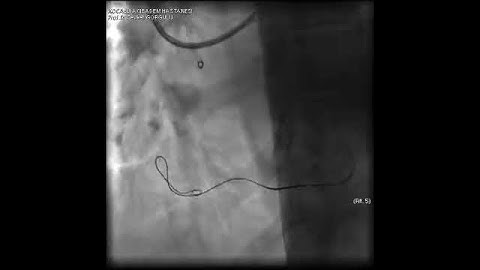

Aortic dissection and radial rupture during retrograde CTO PCI: Management of complications VİDEO 22